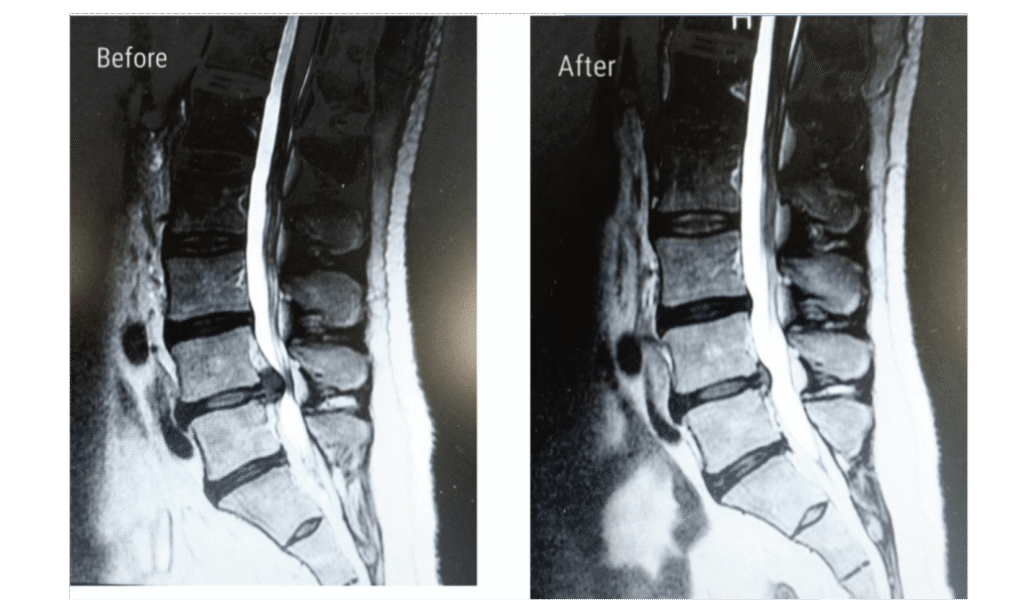

There were improvements of disc height in 27 (72.97%) patients, ranging from 1.1 up to 5.3 mm,with a mean of 2.31±1.24 mm. LBP was improved in 29 (74.36%) patients while radicular pain improved in 33 (84.61%) patients; disc height improved in 27 (72.97%) patients.

There were improvements of disc height in four (11.76%) patients, ranging from 0.1 up to 0.3 mm, with a mean of 0.043±0.091 mm. LBP was improved in 25 (73.53%) patients while radicular pain improved in seven (20.59%) patients; disc height improved in four (11.76%) patients. When we compared both groups, we found that there were nonsignificant differences in the improvement of LBP and a highly significant difference in the improvement of radicular pain and disc height between both groups (Figs 1–4 and Tables 1–4).

Discogenic pain is a major problem in the lumbar area, and it may be caused by progressive annular breakdown and tearing, which cause pain by stimulating pain fibers in the outer one-third of the annulus and by compression over the nerves’ roots. Spinal decompression systems using the DRX9000® have become a noninvasive intervention for the treatment of LBP caused by disc protrusion or herniation by expanding the intervertebral space and reducing the disc protrusion. Our study showed that there was an improvement in back pain and lower extremities’ radicular pain with the decompression system; the improvement was more significant in lower extremities’ pain than back pain.

Figure 1

There was a significant improvement in the disc heights of the majority of patients by the decompression system. Comparing with the control group, we found highly significant improvement in patients treated with the decompression system with regard to radicular pain and disc height compared with other physiotherapy modalities. Our study was in agreement with Richmond et al. [7] who stated that Non-surgical Spinal Decompression.